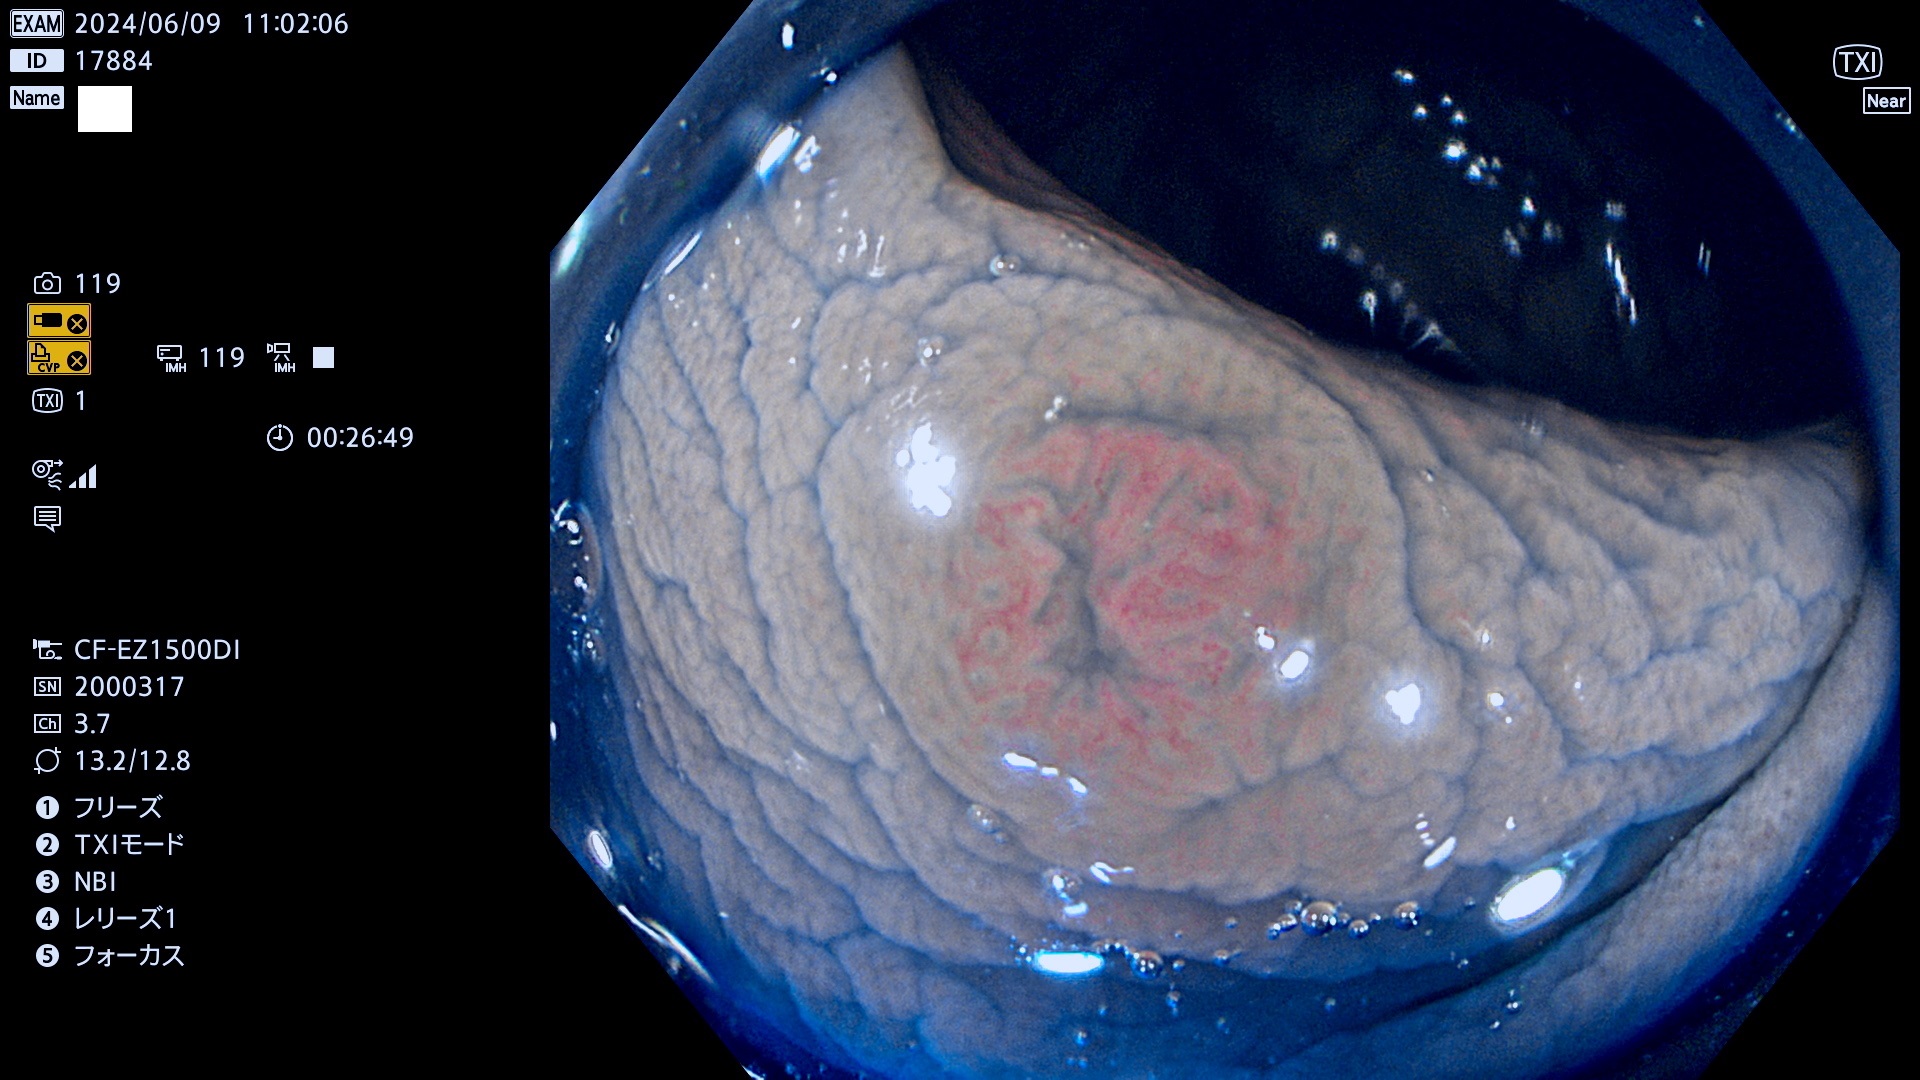

今週のUb、Uc型腺腫

表面型腺腫(Flat Adenoma)の中で、完全に平坦な物をUb、陥凹している物をUcと呼びます。平坦隆起型(Ua)よりも、発見が難しく危険な病変です。

毎週の検査(木・金・土・日)に発見されたUb、Uc型・腺腫を、その週の日曜の夜にUPし1週間、提示します。

抽出の対象期間 2024年6月6日〜6月10の5日間(50件の検査)7件 (7/50=14%)